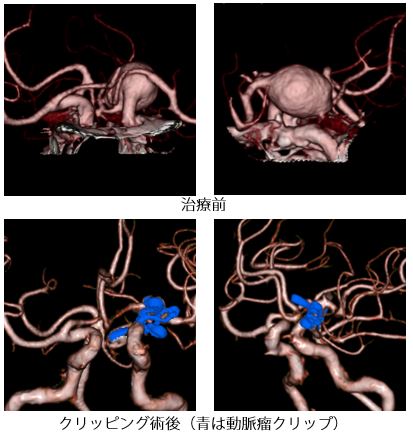

部位や大きさによっては血管内治療より開頭手術の方が適している動脈瘤もあります。開頭クリッピング術では、動脈瘤をチタン製のクリップで挟み動脈瘤内部への血液の流入を遮断し破裂を予防します。動脈瘤そのものから大事な血管が出ている場合や、動脈瘤が周囲の神経や脳を圧迫しているような場合も、開頭手術の方がより安全で再発リスクが低いと考えられます。